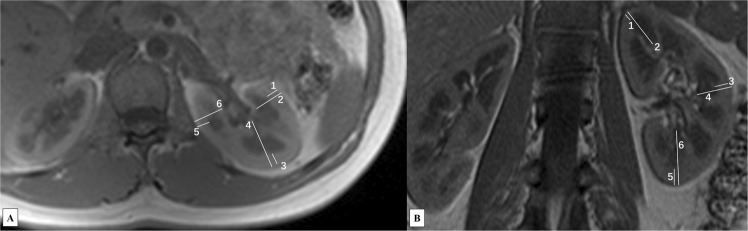

Multiparametric MR images and ROI locations are demonstrated in Fig. 1. Six ROIs were drawn from upper to lower pole in the cortex and medulla respectively on DW (b = 0) image (Fig. 1A), and the corresponding ROIs’ values in ADC map (Fig. 1B) and FA color map (Fig. 1C) were acquired automatically. Similarly, ROIs were drawn from upper to lower pole in the cortex and medulla respectively on T2* map (Fig. 1D). The reconstructed fractional anisotropy (FA) tractography (Fig. 1E) of both kidneys shows the orientation of medullary tubules orienting to the renal hilum. There were no differences observed between the renal cortical thickness (RCT), parenchymal thickness (PT), ratio of cortex to parenchyma (CPR), R2*, apparent diffusion coefficient (ADC) and FA values of the left and right kidney. Figure 2 demonstrates the comparisons of RCT and PT in different areas of the kidney, which shows that RCT and PT of both coronal upper and lower poles are significantly higher than that of axial anterior and posterior areas, respectively (all p < 0.001).

Figure 1.

Coronal MR images of a 27-year old female. Six ROIs were drawn from upper to lower pole in the cortex and medulla respectively on DW (b = 0) image (A). The corresponding ROIs’ values in ADC map (B) and FA color map (C) were acquired automatically. Similarly, six ROIs were drawn from upper to lower pole in the cortex and medulla respectively on T2* map (D). The reconstructed FA Tractography of both kidneys (E) shows the orientation of medullary tubules. Note: Number 1 to 6 represent ROIs in the cortex, and number 7 to 12 in the medulla.

Analysis of the maps for BOLD and DW imaging was performed. In each kidney, 6 circular regions of interest (ROIs) with a fixed 21-voxel diameter were manually placed in the upper, middle and lower poles of bilateral renal cortex and medulla for the measurement of R2*, ADC, and FA values (Fig. 1). The visible blood vessels, renal pelvis, cysts, tissue boundaries and areas of heterogeneous signal intensity were avoided. T2* value was obtained in T2* maps, then an average R2* value (=1/T2*) was determined for each ROI. ROIs were drawn on the diffusion weighted images (b = 0 s/mm2) to exhibit adequate anatomic details. Then, they were automatically matched on ADC and FA maps for quantification. Diffusion tensor maps were imported to Neuro 3D workstation for analysis.